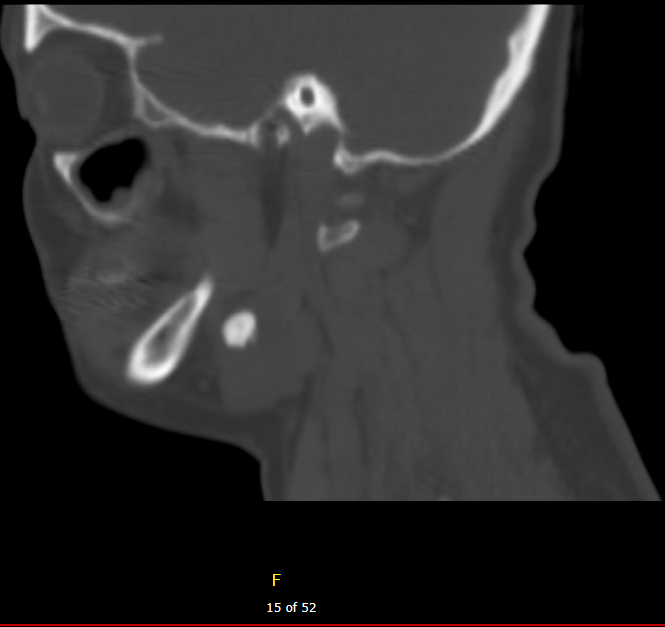

Diagnostic testing. A computed tomography (CT) scan without contrast was performed shortly after initial presentation to further investigate the cause of her chronic pain and swelling (Figures 1 and 2). The CT revealed a calculus in the dorsal aspect of the left submandibular duct that measured approximately 1.1 x 0.8 x 1.1 cm in anteroposterior, transverse, and coracoclavicular dimensions, respectively. The nasopharynx and oropharynx were within normal limits. Soft tissue planes of the adjacent parapharyngeal spaces were maintained. No distinct radiopaque calculus was noted otherwise along the course of Wharton or Stensen ducts, nor was there evidence of distention of the proximal aspect of Wharton duct on the left despite the described calculus. The submandibular and parotid glands otherwise appear to be within normal limits. Specifically, there was no evidence of acute sialadenitis. The hypopharyngeal, supraglottic, glottic, and subglottic airways were within normal limits. The soft tissue planes of the upper neck were otherwise maintained. No significant lymphadenopathy was seen by size criteria. Based on these results, it was confirmed that the patient had a sialolith of the left submandibular gland.

Figure 2. A bone mode/hard tissue condition sagittal head CT imaging of 12 mm submandibular sialolith.